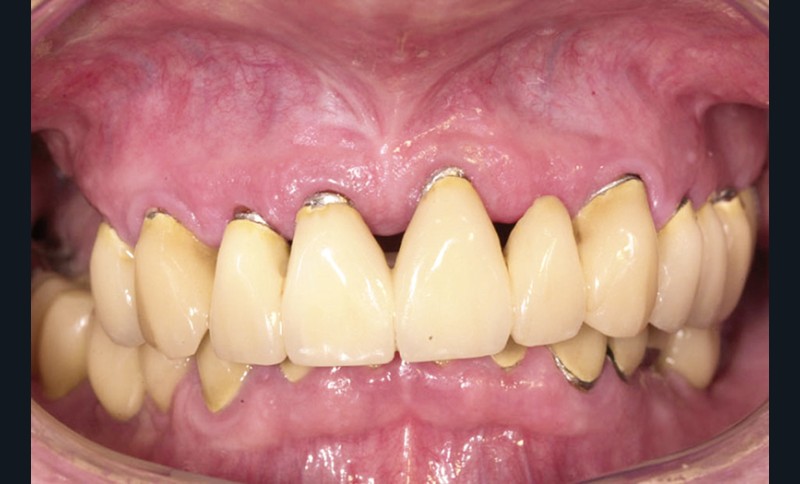

Lors de la maintenance de 2016, le contrôle de plaque de la patiente est toujours excellent et les tissus implantaires ne présentent pas de signes inflammatoires(fig. 2a et b).